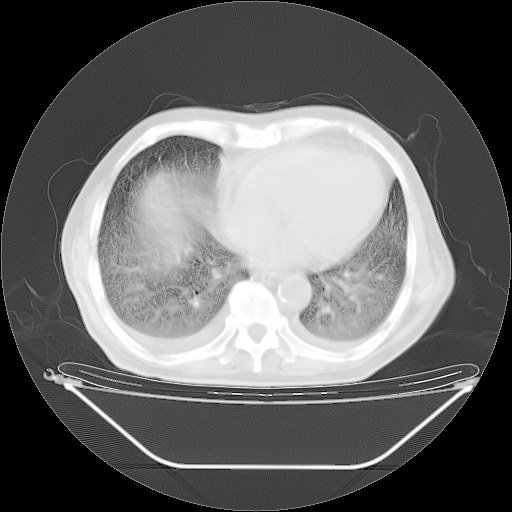

胸腹部CT,诊断意见:左上肺叶钙化灶、左侧胸膜局限性增厚并钙化、胆囊炎。描述部分肺组织呈磨玻璃样改变。